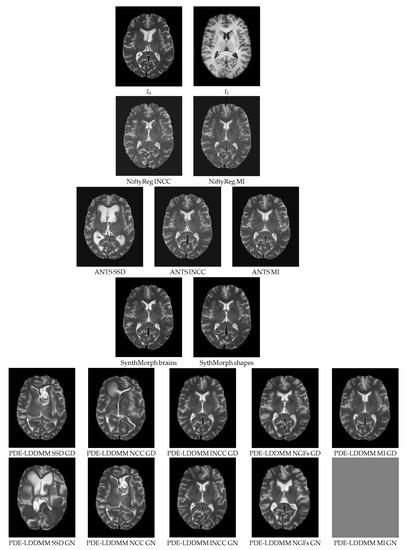

5.1.3. Qualitative Assessment